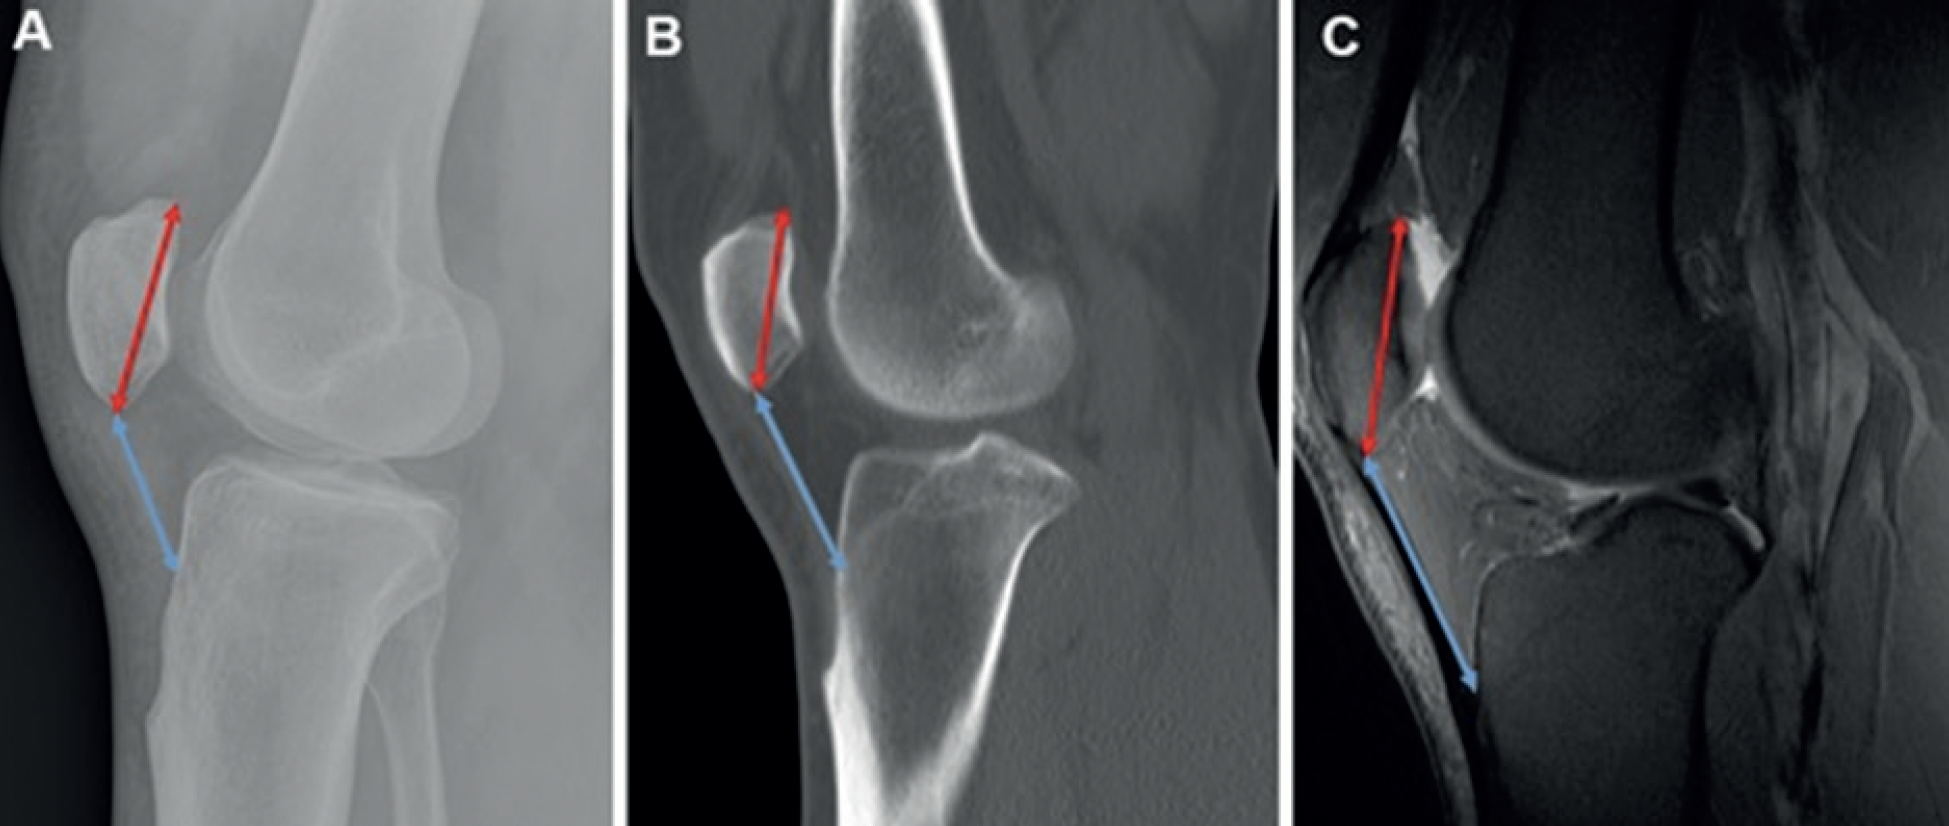

The study assessed two widely used patellar height indices: the Insall– Salvati and Blackburne–Peel ratios. For the Insall–Salvati method (Figure 2), patellar length was measured from the posterior superior articular margin to the most distal anterior tip, excluding osteophytes. The longest diagonal length was used. Tendon length was measured from the distal anterior patella to the tibial tuberosity. In cases of tendon laxity, a straight-line measurement was applied. The Insall– Salvati ratio was calculated as the tendon length divided by patellar length, providing a standardized assessment of patellar height.

Figure 2

Figure 2. CT = Computed tomography; IS = Insall–Salvati; MRI = Magnetic resonance imaging; X-Ray=Radiograph. A. Lateral radiograph depicting the IS measurements. The patellar length (red line with arrows at both ends) is measured from the tip of the posterior articular margin to the distal anterior tip of the patella. The patellar tendon length (blue line with arrows at both ends) is obtained by measuring from the distal anterior tip of the patella to its insertion on the tibial tuberosity, where the tibial tuberosity is most prominent, B. CT on the bone window illustrating the IS measurements. Although the patellar tendon appears slightly curved near the tibial insertion, the straight-line distance from the patellar attachment to the tibial tuberosity insertion is utilized (blue line with arrows at both ends). The patellar length is also indicated (red line with arrows at both ends), C. Sagittal fat-saturated proton-density MRI demonstrating the measurements of the patellar length (red line with arrows at both ends) and the patellar tendon length (blue line with arrows at both ends) according to the IS method